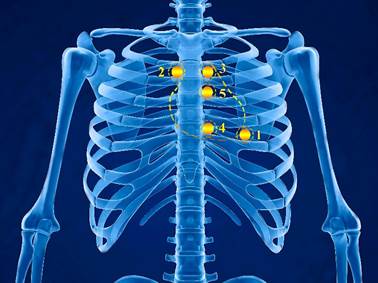

б) проєкції клапанів серця на грудну стінку і точки їх вислуховування (мал. 1):

Мал. 1. Точки аускультації (прослуховування) серця

1-а – точка верхівкового поштовху (проєкція лівого атріовентрикулярного отвору, вислуховується мітральний клапан);

2-а – точка в II міжребер’ї безпосередньо у правого краю груднини (вислуховуються клапани аорти і гирла аорти);

3-а – точка в II міжребер’ї безпосередньо у лівого краю груднини (вислуховуються клапани легеневої артерії);

4-а – нижня третина груднини у основи мечоподібного відростка і місця прикріплення V ребра до правого краю груднини (проєкція правого атріовентрикулярного отвору, вислуховується тристулковий клапан);

5-а – на рівні III міжребір’я у лівого краю груднини (додаткова точка вислухування аортальних клапанів).